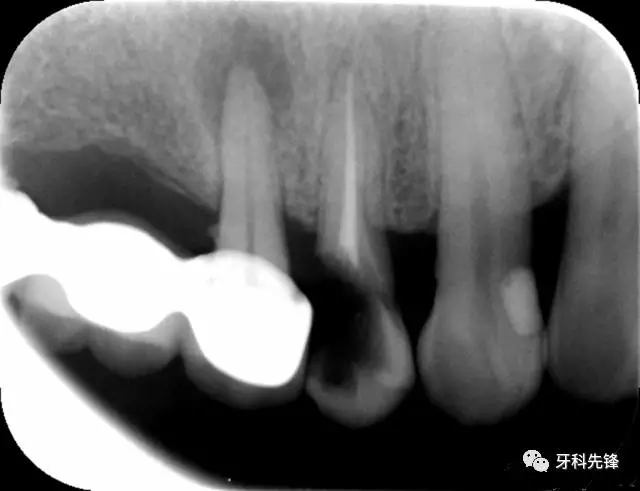

X 示:15  根管透射,根尖有陰影

14  根管阻射,恰填,無異常

46  根管阻射,恰填,根分叉骨密度降低,近中根尖陰影較大

圖1 術(shù)前X光片